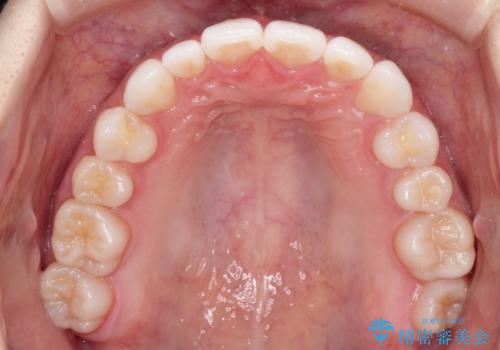

インビザラインで出っ歯を改善する 抜歯をしないinvisalign治療

- 非抜歯・遠心移動による前突の改善をマウスピースにて計画した。

非抜歯矯正の場合、大きく前歯を下げることはできませんが、奥歯の遠心移動や歯のサイズダウンにより歯軸を立て、見かけ上の出っ歯感をある程度改善することができます。